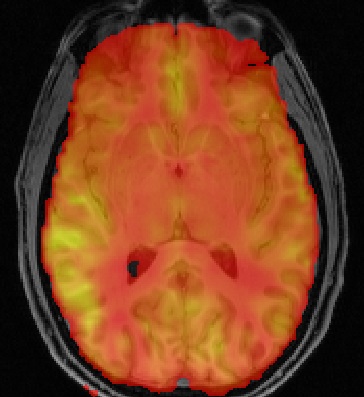

Arterial Spin Labeling (ASL) MRI is a non-invasive method for the quantification of perfusion. Analysis of ASL data typically requires the inversion of a kinetic model of label inflow along with a separate calculation of the equilibrium magnetization of arterial blood. The BASIL toolbox provides a means to do this based on Bayeisan inference principles. The method was orginally developed for multi delay (inversion time) data where it can be used to greatest effect, but is also sufficiently fleixble to deal with the widely used single delay form of acquisition.

For single delay ASL data kinetic model inversion is realtively trivial and solutions to the standard model have been described int he literature. However, it is becoming increasingly common to aquire ASL data at multiple times post-inversion and fit the resultant data to a kinetic curve model. This permits problems in perfusion estimation associated with variable bolus arrival time to be avoided, since this becomes a paramter of the model whose value is determined from the data. Commonly the model fitting will be performed with a least squares technique providing parameter estimates, e.g. perfusion and bolus arrival time. In contrast to this BASIL uses a (fast) Bayesian inference method for the model inversion, this provides a number of advantages: